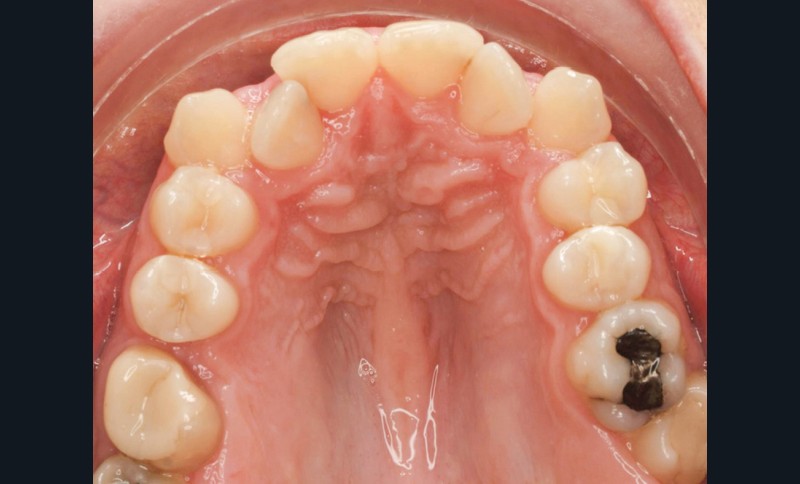

Diagnostic (fig. 1a-g)

La patiente présente une classe III squelettique dans un contexte hyperdivergent associée à une endoalvéolie maxillaire, un articulé inversé antérieur, une rétroversion incisive maxillaire, des rapports de classe I canine bilatérale, une absence de 16 et 36.

Au niveau esthétique, le profil est rectiligne. La lèvre supérieure est plus effacée, en retrait par rapport à la lèvre inférieure. De face et de profil, la mandibule paraît massive et le maxillaire effacé : le manque de soutien de la lèvre supérieure contribue à cette impression.

Le sourire est étroit, dégradé par les malpositions dentaires.

Au niveau fonctionnel, il existe un pro-glissement mandibulaire et un articulé inversé antérieur. Le profil téléradiographique montre en occlusion des rapports labiaux et un profil de classe III plus marqué que sur photographies.